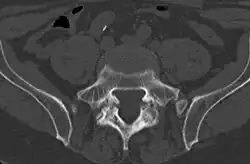

Computed tomography

Commonly known as a CT Scan or CAT scan, this form of imaging uses x-rays to produce multiple cross-sectional images, or "slices", through a part of the body. This allows a physician to evaluate the body in greater detail than an x-ray allows. For this reason the CT scan is much more accurate in detecting spondylolysis than an x-ray. Bone scintigraphy combined with CT scan is considered the reference standard, which means that it is best at detecting spondylolysis.[16][18]